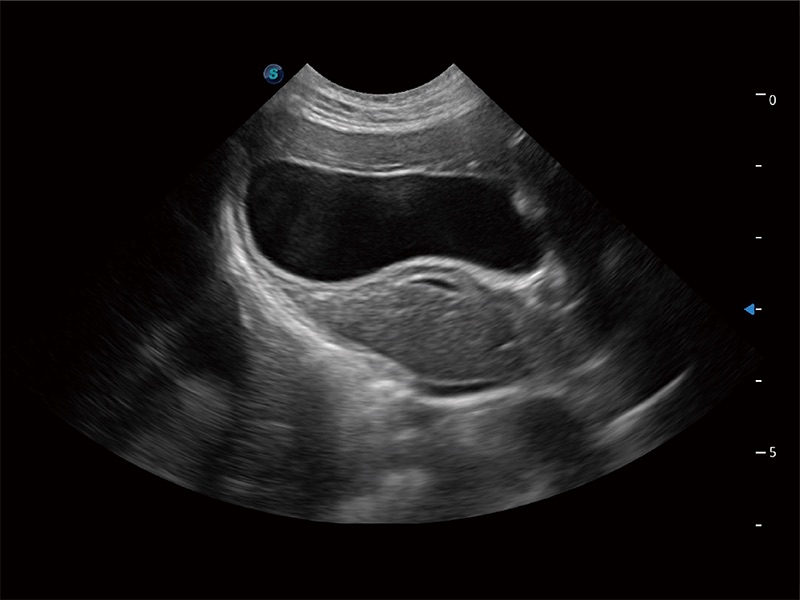

动物是人类最亲密的朋友和最值得信赖的伙伴。球速体育入口也一直致力于探索动物专用的超声影像解决方案。全新推出的ProPet系列,是球速体育入口在动物超声影像智能化、专业化、精准化的一次跨越式革新。动物不能用言语来表述自己的不适,通过超声影像,ProPet系列搭建了动物医生与不同物种沟通的“桥梁”,为动物医生注入了“治愈之力”。 ProPet 80 是球速体育入口匠心打造的一款高端动物专用彩超,采用性能卓越的全新硬件架构,极大提升超声系统的运行效率和数据处理能力,帮助动物医生从容应对日益增多的挑战性病例和日益多样化的临床需求。

高性能和先进的临床应用工具可以为动物医生提供临床信心。ProPet 80 搭载了先进的腹部和浅表应用工具,帮助医生在日常临床实践中发挥前所未有的作用。

ProPet 80 全新的动物超声智能软件和丰富的探头群,为动物医生提供了高清晰度和精细分辨率的图像,无论在宠物、马科、畜牧还是实验室动物等应用中都可以轻松应对,为您的日常工作带来满意的体验。